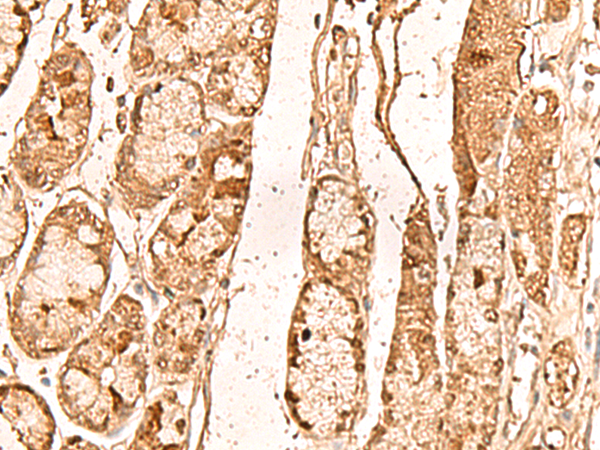

IHC positive control:

|

Human liver cancer

IHC Recommend dilution:

50-300